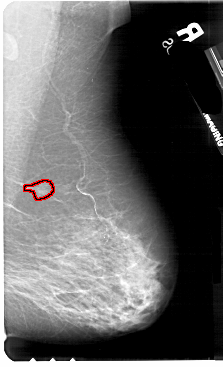

A_1700_1.LEFT_CC

LEFT_CC LINES 5491 PIXELS_PER_LINE 3151 BITS_PER_PIXEL 12 RESOLUTION 43.5 NON_OVERLAY

FILE: A_1700_1.RIGHT_CC.OVERLAY

TOTAL_ABNORMALITIES 1

ABNORMALITY 1

LESION_TYPE MASS SHAPE IRREGULAR MARGINS SPICULATED

ASSESSMENT 5

SUBTLETY 1

PATHOLOGY MALIGNANT

TOTAL_OUTLINES 2

BOUNDARY

CORE